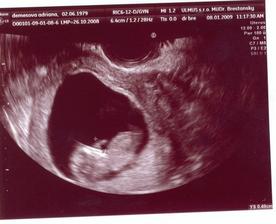

15.01.2009 nás čaká ďalšie sono:D, už teraz sa teškáme....08.01.2009 špinenie, panika...tak šups doktorovi - predpísal nám Utrogestan, MagneB6 a Ascorutin. Máme si dávať denne dva citróny a dve lyžičky medíku. Dostali sme štipľavú injekciu, ale bábätku našťastie veselo bije srdiečko...a máme pre istotu aj fotečky:D

15.1.2009 sono + fotecka. bábätko robí kotrmelce, máva ručičkami a nožičkami (nech sa blázni, kým má miesto:D). všetko vyzerá byť ok. akurát na ľavom vaječníku mi dr.objavil cystu. hádam bude všetko ok.....